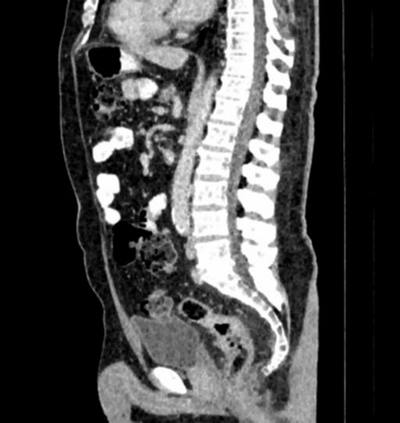

Due to the constraints of the imaging device and high cost in operation time, computer tomography (CT) scans are usually acquired with low intra-slice resolution. Improving the intra-slice resolution is beneficial to the disease diagnosis for both human experts and computer-aided systems. To this end, this paper builds a novel medical slice synthesis to increase the between-slice resolution. Considering that the ground-truth intermediate medical slices are always absent in clinical practice, we introduce the incremental cross-view mutual distillation strategy to accomplish this task in the self-supervised learning manner. Specifically, we model this problem from three different views: slice-wise interpolation from axial view and pixel-wise interpolation from coronal and sagittal views. Under this circumstance, the models learned from different views can distill valuable knowledge to guide the learning processes of each other. We can repeat this process to make the models synthesize intermediate slice data with increasing inter-slice resolution. To demonstrate the effectiveness of the proposed approach, we conduct comprehensive experiments on a large-scale CT dataset. Quantitative and qualitative comparison results show that our method outperforms state-of-the-art algorithms by clear margins.